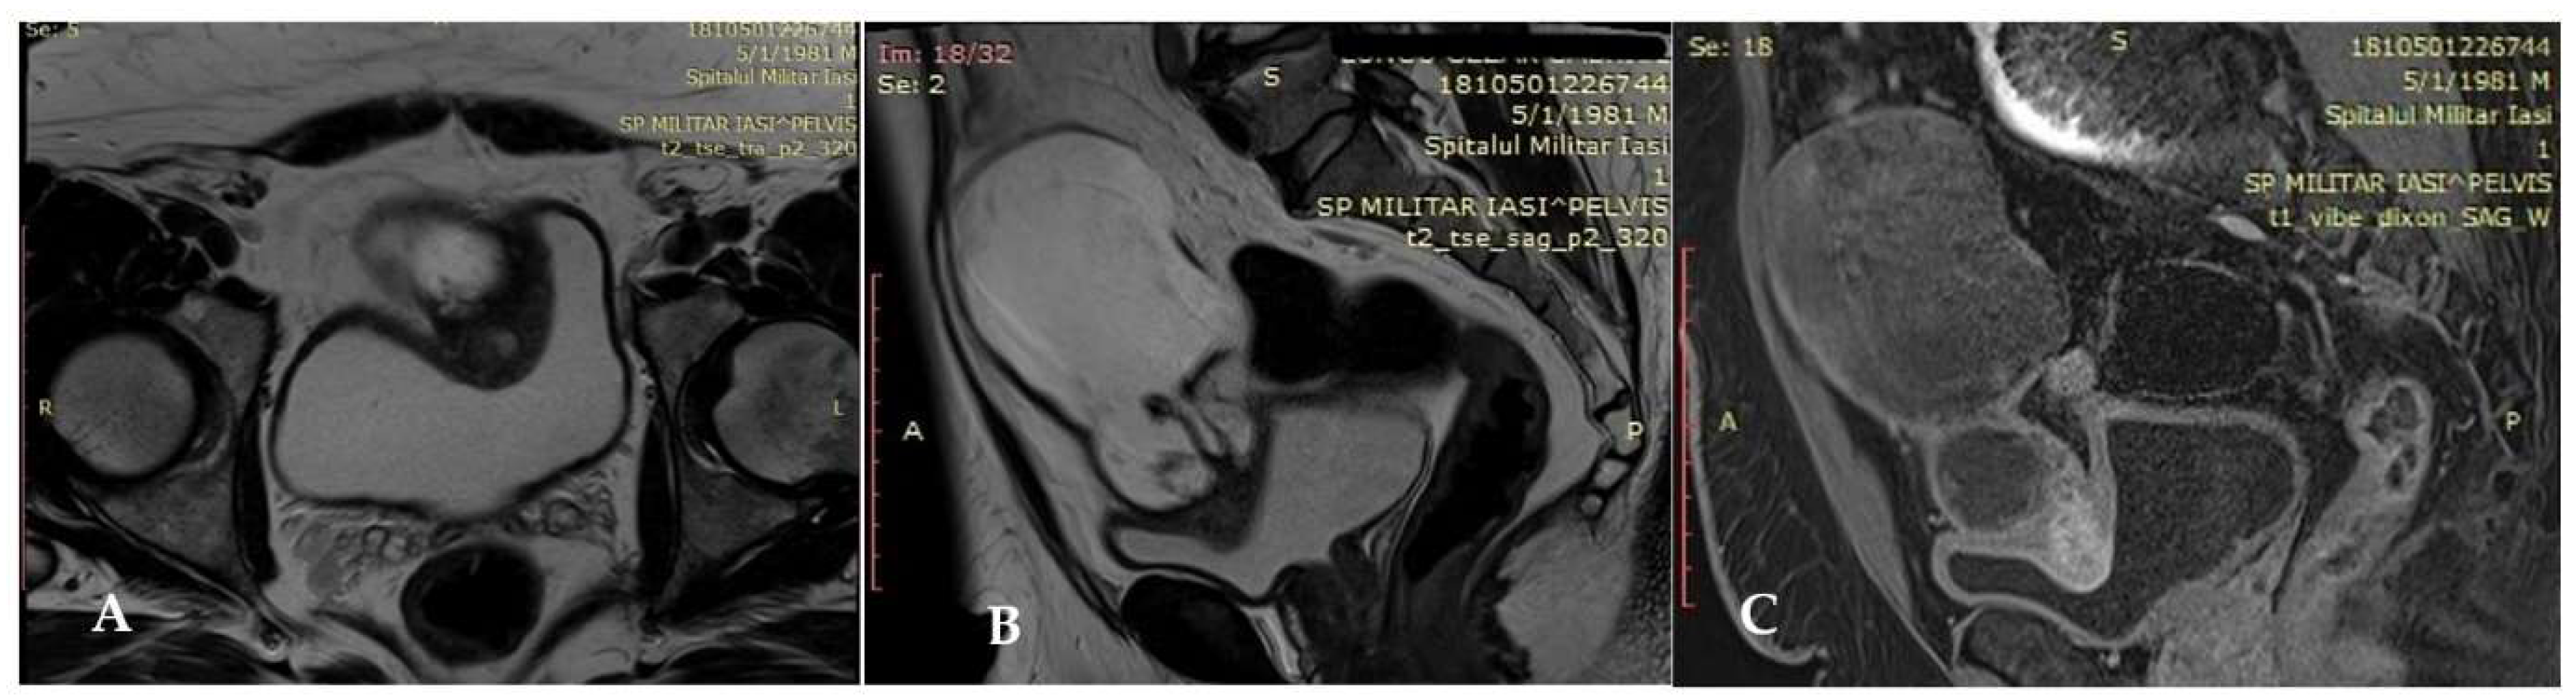

2.2. Imaging Findings